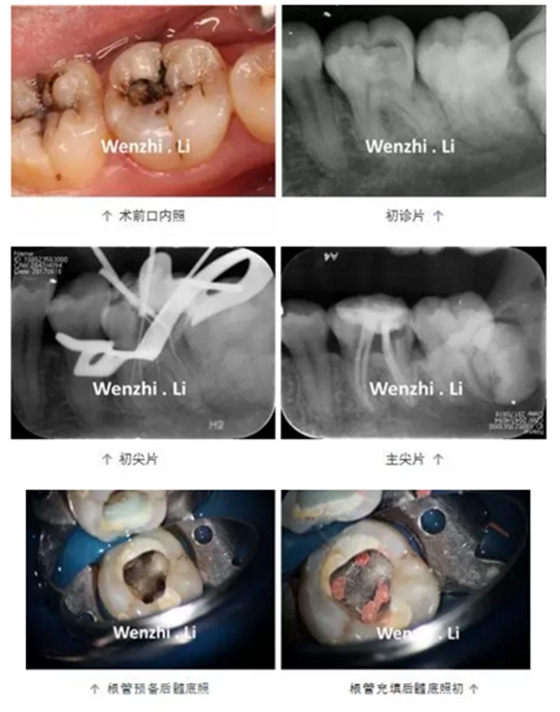

病例三 | 下頜第一磨牙彎曲根管一例

下頜第一磨牙彎曲

根管一例

首都醫(yī)科大學(xué)附屬口腔醫(yī)學(xué)院 李文芝

指導(dǎo)教師:張琛

年輕女性患者因左下后牙間斷性自發(fā)性疼痛及冷熱刺激痛1個(gè)月就診,診斷為36慢性牙髓炎。局麻下,橡皮樟隔離下去腐,開髓,揭頂,可見髓腔鈣化,顯微鏡下超聲去除鈣化物,探及4個(gè)根管口,拍攝初尖銼片顯示MB根管為重度彎曲根管、DL根管彎曲極近根尖區(qū),X線片上未顯示。17% EDTA配合PathFile、Protaper NEXT 鎳鈦器械預(yù)備根管,實(shí)現(xiàn)連續(xù)錐度的根管形態(tài),5.25% NaClO沖洗,連續(xù)波熱牙膠根管充填4個(gè)根管,拍攝根充片,X線片顯示根充恰填。隔濕干燥,自酸蝕粘接,SDR+納米樹脂充填。

1.下頜第一磨牙解剖形態(tài);84%的下頜第一磨牙根管為彎曲根管,大 多數(shù)的下頜第一磨牙為DL根管彎曲,且彎曲程度不一。DL根管通常向遠(yuǎn)中頰側(cè)彎曲彎曲根管預(yù)備并發(fā)癥;

2. 預(yù)備彎曲根管技巧:器械預(yù)彎,建立直線通路;使用柔韌性及抗疲勞強(qiáng)度更好的鎳鈦旋轉(zhuǎn)器械;足量及有效的超聲根管蕩洗;連續(xù)波加壓充填技術(shù)。PathFile柔韌性好,在足量根管潤滑劑下,可以順暢的通過根管彎曲部。Protaper NEXT 具有較好的柔韌性及抗疲勞強(qiáng)度,可降低預(yù)備彎曲根管時(shí)出現(xiàn)根管偏移的風(fēng)險(xiǎn)。